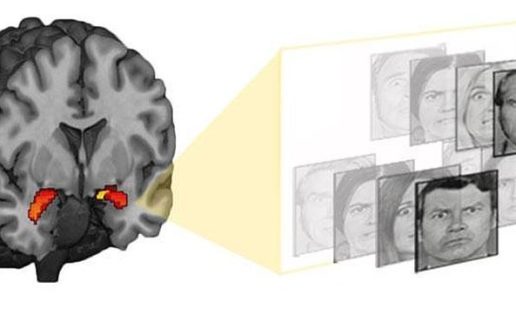

La técnica mide la reacción de la zona del cerebro que responde a las amenazas ante fotografías de rostros enfadados o asustados

Científicos de la Universidad de Duke tienen una nueva estrategia para predecir si las personas tienen un mayor riesgo de depresión o ansiedad después de los acontecimientos estresantes, y por lo tanto podrían beneficiarse de intervenciones tempranas para salvaguardar su salud mental. Según el trabajo hay una correlación entre la forma en que responde el cerebro ante fotos de rostros enojados o temerosos y la capacidad de la persona que las ve para recuperarse de los estresores psicólogicos que acechan en la vida cotidiana, como rupturas de pareja o reveses económicos.

Y al parecer es tan sencillo como hacer una resonancia magnética funcional. Según el estudio, los participantes cuyas resonancias registraronmayor actividad en su amígdala -un grupo de neuronas relevantes en la detección de amenazas y el recuerdo de la información negativa– se evaluaron a sí mismos más propensas a la depresión o ansiedad ante sucesos estresantes con los que se habían enfrentado hasta cuatro años después de participar en el estudio. “Encontramos que las respuestas más fuertes de la amígdala predicen mayores síntomas de depresión y ansiedad en respuesta al estrés en el futuro, en un plazo de 1 a 4 años”, explica el autor principal, Johnna Swartz de la Universidad de Duke.